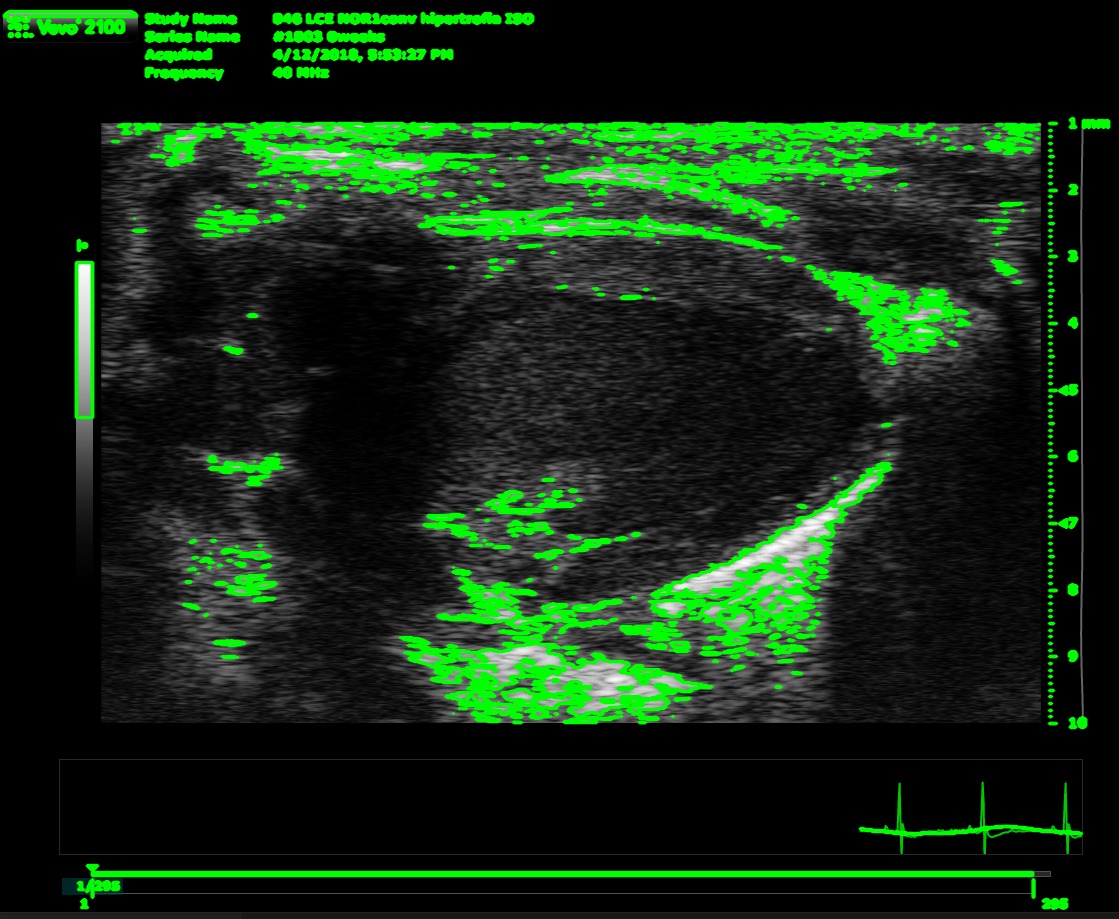

Its a CLI's program where have to give a psla and sax dicom files path. Then gets some variables from the files to throw some conclusions (if it's a healthy heart or not) and also it save it as excel file.

We built it as a python project with its virtual environment with the requirements needed, also needs a special program called Theseract that it is a optical character recognition open source to get the BPM from the files, the rest of the needed parameters are calculed using opencv mainly.

The most significative challenge that the team ran into consisted in the identification of the contourns of the image. Differenciating between the underside and the outer layer of the blood vessel ended up being an arduous task